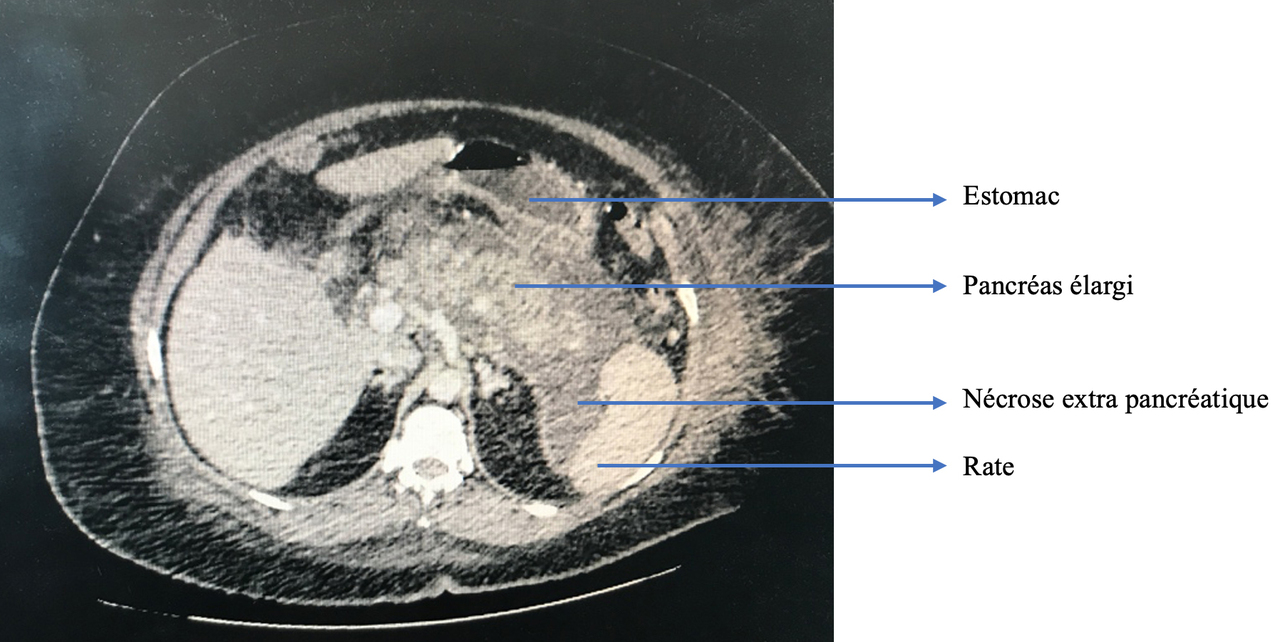

La douleur de la pancréatite est épigastrique irradiant dans le dos, majorée par la respiration profonde et la position antalgique est en chien de fusil.

Causes de pancréatite aiguë :

– lithiasique : la plus fréquente ;

Ces 2 causes représentent environ 80 % des pancréatiques aiguës.